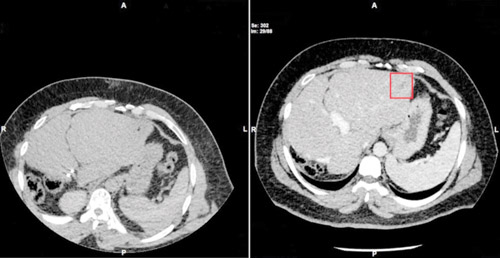

ذكر ذلك البروفيسور الدكتور سليمان الماجد نائب الرئيس للشؤون الطبية والتمريض بالمجموعة والمدير الطبي بالمستشفى، والذي أضاف بأنه فور وصول المريض للعيادة تم إخضاعه لبرنامج من الفحوصات المخبرية والتصوير المقطعي (C.T Scan)، وكذلك التصوير بالرنين المغناطيسي (M.R.I.) على منطقة البطن والصدر، موضحاً أن نتائج الفحوصات أوضحت بدقة وجود 7 أورام بالكبد تتراوح أحجامها بين الصغيرة والمتوسطة بالإضافة إلى وجود ورم بالقولون السيني بحجم (2×3×3) سم.

وأشار الدكتور الماجد إلى أن المتابعة الدورية للمريض أبانت وجود نمو لورم جديد في الكبد دائري الشكل بقطر 1 سم، مؤكداً على أنه تم علاج هذا الورم بدون تدخل جراحي من خلال تقنية الكي والتي تتم باستخدام موجات التردد اللاسلكية (Radio Frequency Applications) ، مؤكداً على أنه بعد الانتهاء من الإجراء الجراحي، تم إخضاع المريض لفحص باستخدام التصوير المقطعي والرنين المغناطيسي على كامل الجسم للاطمئنان على وضعه الصحي ولله الحمد كانت النتائج مبشرة واتضح عدم نمو أية أورام أخرى.